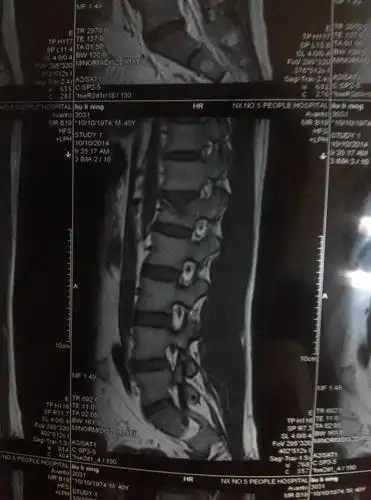

腰椎间盘突出

腰椎间盘突出症是骨科常见病之一,约1/5的腰腿痛病人是腰椎间盘

腰椎间盘可发生突出,脱出或游离,并压迫神经根一,症状腰椎间盘突出

腰椎间盘突出 写美篇椎间盘,顾名思义就是我们人体脊椎之间像圆盘一样